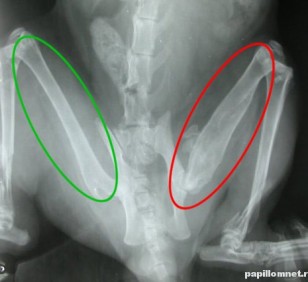

Изображение обыкновенной мозоли, которая заполнена жидкостью